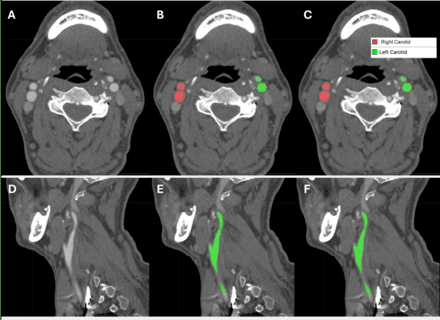

Results: 422 cases were used for training and 106 for testing. In testing data, the fully automated tool achieved excellent performance for bilateral segmentation of carotid lumens (Dice 0.91, 95%CI:0.90-0.92, e.g. Figure 1). For detection of calcific and hypodense plaque components, respectively, the model achieved sensitivity of 96.5% (95%CI:89.3-99.1%) and 97.3% (89.6-99.5%), specificity of 95.2% (74.1-99.8%) and 75.8% (57.4-88.3%), positive predictive value of 98.8% (92.6-99.9%) and 89.9% (80.5-95.2%), negative predictive value of 87.0% (65.3-96.6%) and 92.6% (74.2-98.7%), and accuracy of 96.2% (90.1-98.8%) and 90.6% (82.9-95.1%, e.g. Figure 2). Dice score was 0.73 (0.69-0.76) for calcific plaque and 0.53 (0.49-0.57) for hypodense plaque.